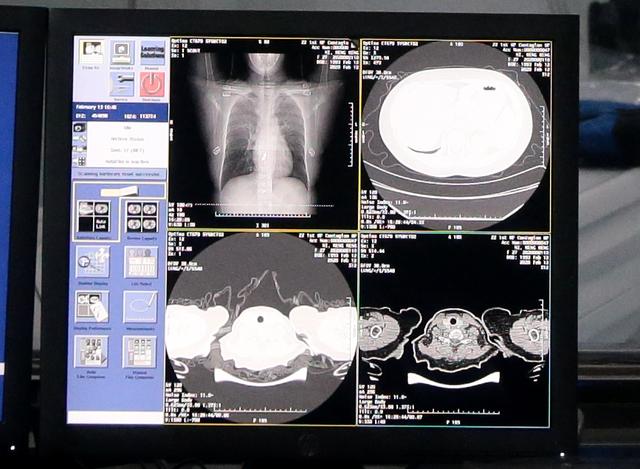

达摩院AI自动识别新冠肺炎病例CT胸片

2月15日,达摩院影像AI率先在“郑州小汤山”岐伯山医院上线。只需20秒,AI就能对新冠疑似患者CT影像做出判读,并量化病症的轻重程度,分析结果准确率高达96%。

到目前为止,CT影像AI已在湖北、上海、广东、江苏、安徽等16个省市近170家医院落地,对34万临床病例做出了诊断。我们之所以能在各大媒体平台上看到实时的确诊数字,少不了阿里“影像科”的一份功劳。